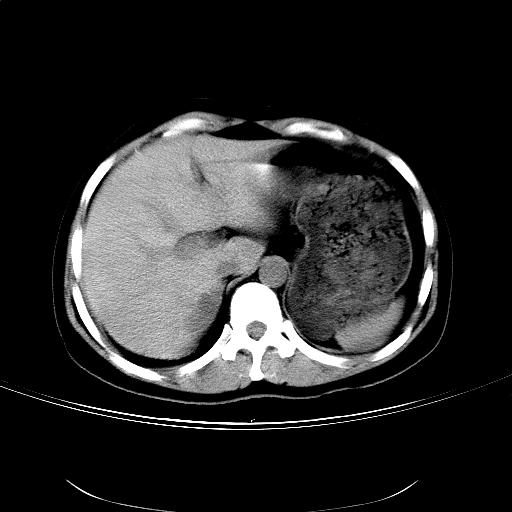

女,36岁,右上腹不适数天。5天后公布结果。

肝左叶有俩原形低密度,边缘光整,内密度均匀一致,考虑小囊肿。

右侧肾上腺区域不规则低密度占位性病变,似乎有俩病灶不完全相连。密度不均匀,内见钙化。首先考虑囊肿,建议增强薄层扫描。

支持1肝内小低密度灶考虑多系囊肿。2右侧肾上腺区低密度结节影,其内见两个小点状钙化灶,低密度影似有分叶或为两个,右肾上部显示不清。考虑右侧肾上腺良性占位病变,请结合临床及超声与增强检查。

比较典型的右侧肾上腺囊肿;肝脏左外叶上段小囊肿。

结果:肾上腺囊肿。